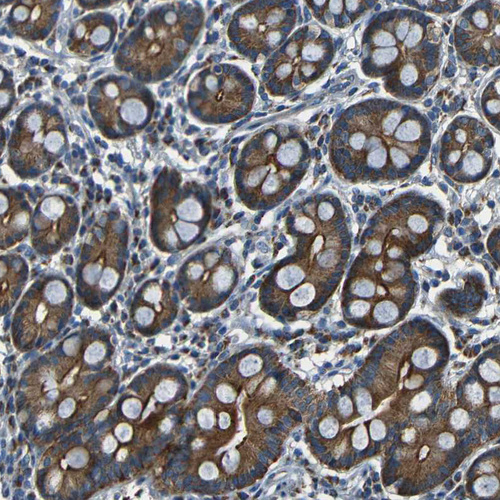

Immunohistochemical staining of human testis shows moderate granular cytoplasm positivity in leydig cells and cells in seminiferous ducts.